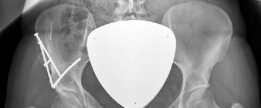

The radiographic evaluation of the dysplastic hip requires a highly standardized and rigorous protocol to accurately quantify the three-dimensional deformity. The initial assessment begins with a standing anteroposterior (AP) radiograph of the pelvis. In this patient, the AP view immediately reveals the hallmark signs of DDH: decreased anterolateral coverage of the femoral head and a broken Shenton line. The broken Shenton line—a step-off between the medial border of the femoral neck and the inferior border of the superior pubic ramus—indicates proximal and lateral migration of the femoral head due to structural instability. Furthermore, we observe an increased Tönnis angle (acetabular inclination) and a significantly reduced Lateral Center Edge Angle (LCEA) of Wiberg, confirming the diagnosis of severe lateral uncoverage.

Beyond the AP pelvis, the False Profile view of Lequesne and de Sèze is mandatory to evaluate anterior coverage, which is frequently deficient in DDH. This view allows for the measurement of the Anterior Center Edge Angle (ACEA). In this patient, the ACEA is markedly reduced, correlating directly with her positive anterior apprehension test and the anterior location of her labral tear. We must also scrutinize the AP radiograph for signs of acetabular retroversion, such as the crossover sign, ischial spine sign, and posterior wall sign. Dysplasia is rarely a simple lack of lateral coverage; it is often a complex, multi-planar deformity where the acetabulum is not only shallow but also maloriented in the sagittal and axial planes.

The most critical functional radiograph in our preoperative workup is the AP Abduction view (often taken with the hip in 20-30 degrees of abduction and slight internal rotation). This view simulates the mechanical effect of a periacetabular osteotomy by effectively "rotating" the femoral head deeper into the acetabular dome. In this patient's case, the abduction view demonstrates excellent achievable congruency and congruity. The joint space becomes symmetric, and the femoral head centralizes perfectly within the socket. This is the ultimate litmus test for joint preservation: if the abduction view shows persistent incongruency or a "hinging" effect where the joint space narrows medially, a reorientation osteotomy may be contraindicated, as it would simply rotate a misshapen socket over a misshapen head, accelerating arthrosis.

With the acetabular fragment now mobile, a 5.0mm Schanz pin is placed into the supra-acetabular region to act as a joystick. The fragment is mobilized and rotated laterally and anteriorly to achieve the pre-planned coverage. We also intentionally medialize the fragment to optimize the abductor lever arm. The hip is taken through a full range of motion to ensure there is no iatrogenic anterior impingement. Fluoroscopy is utilized extensively at this stage. We obtain AP, false profile, and obturator oblique views to confirm the correction of the LCEA, ACEA, and Shenton's line, and to ensure the joint space remains perfectly congruent.